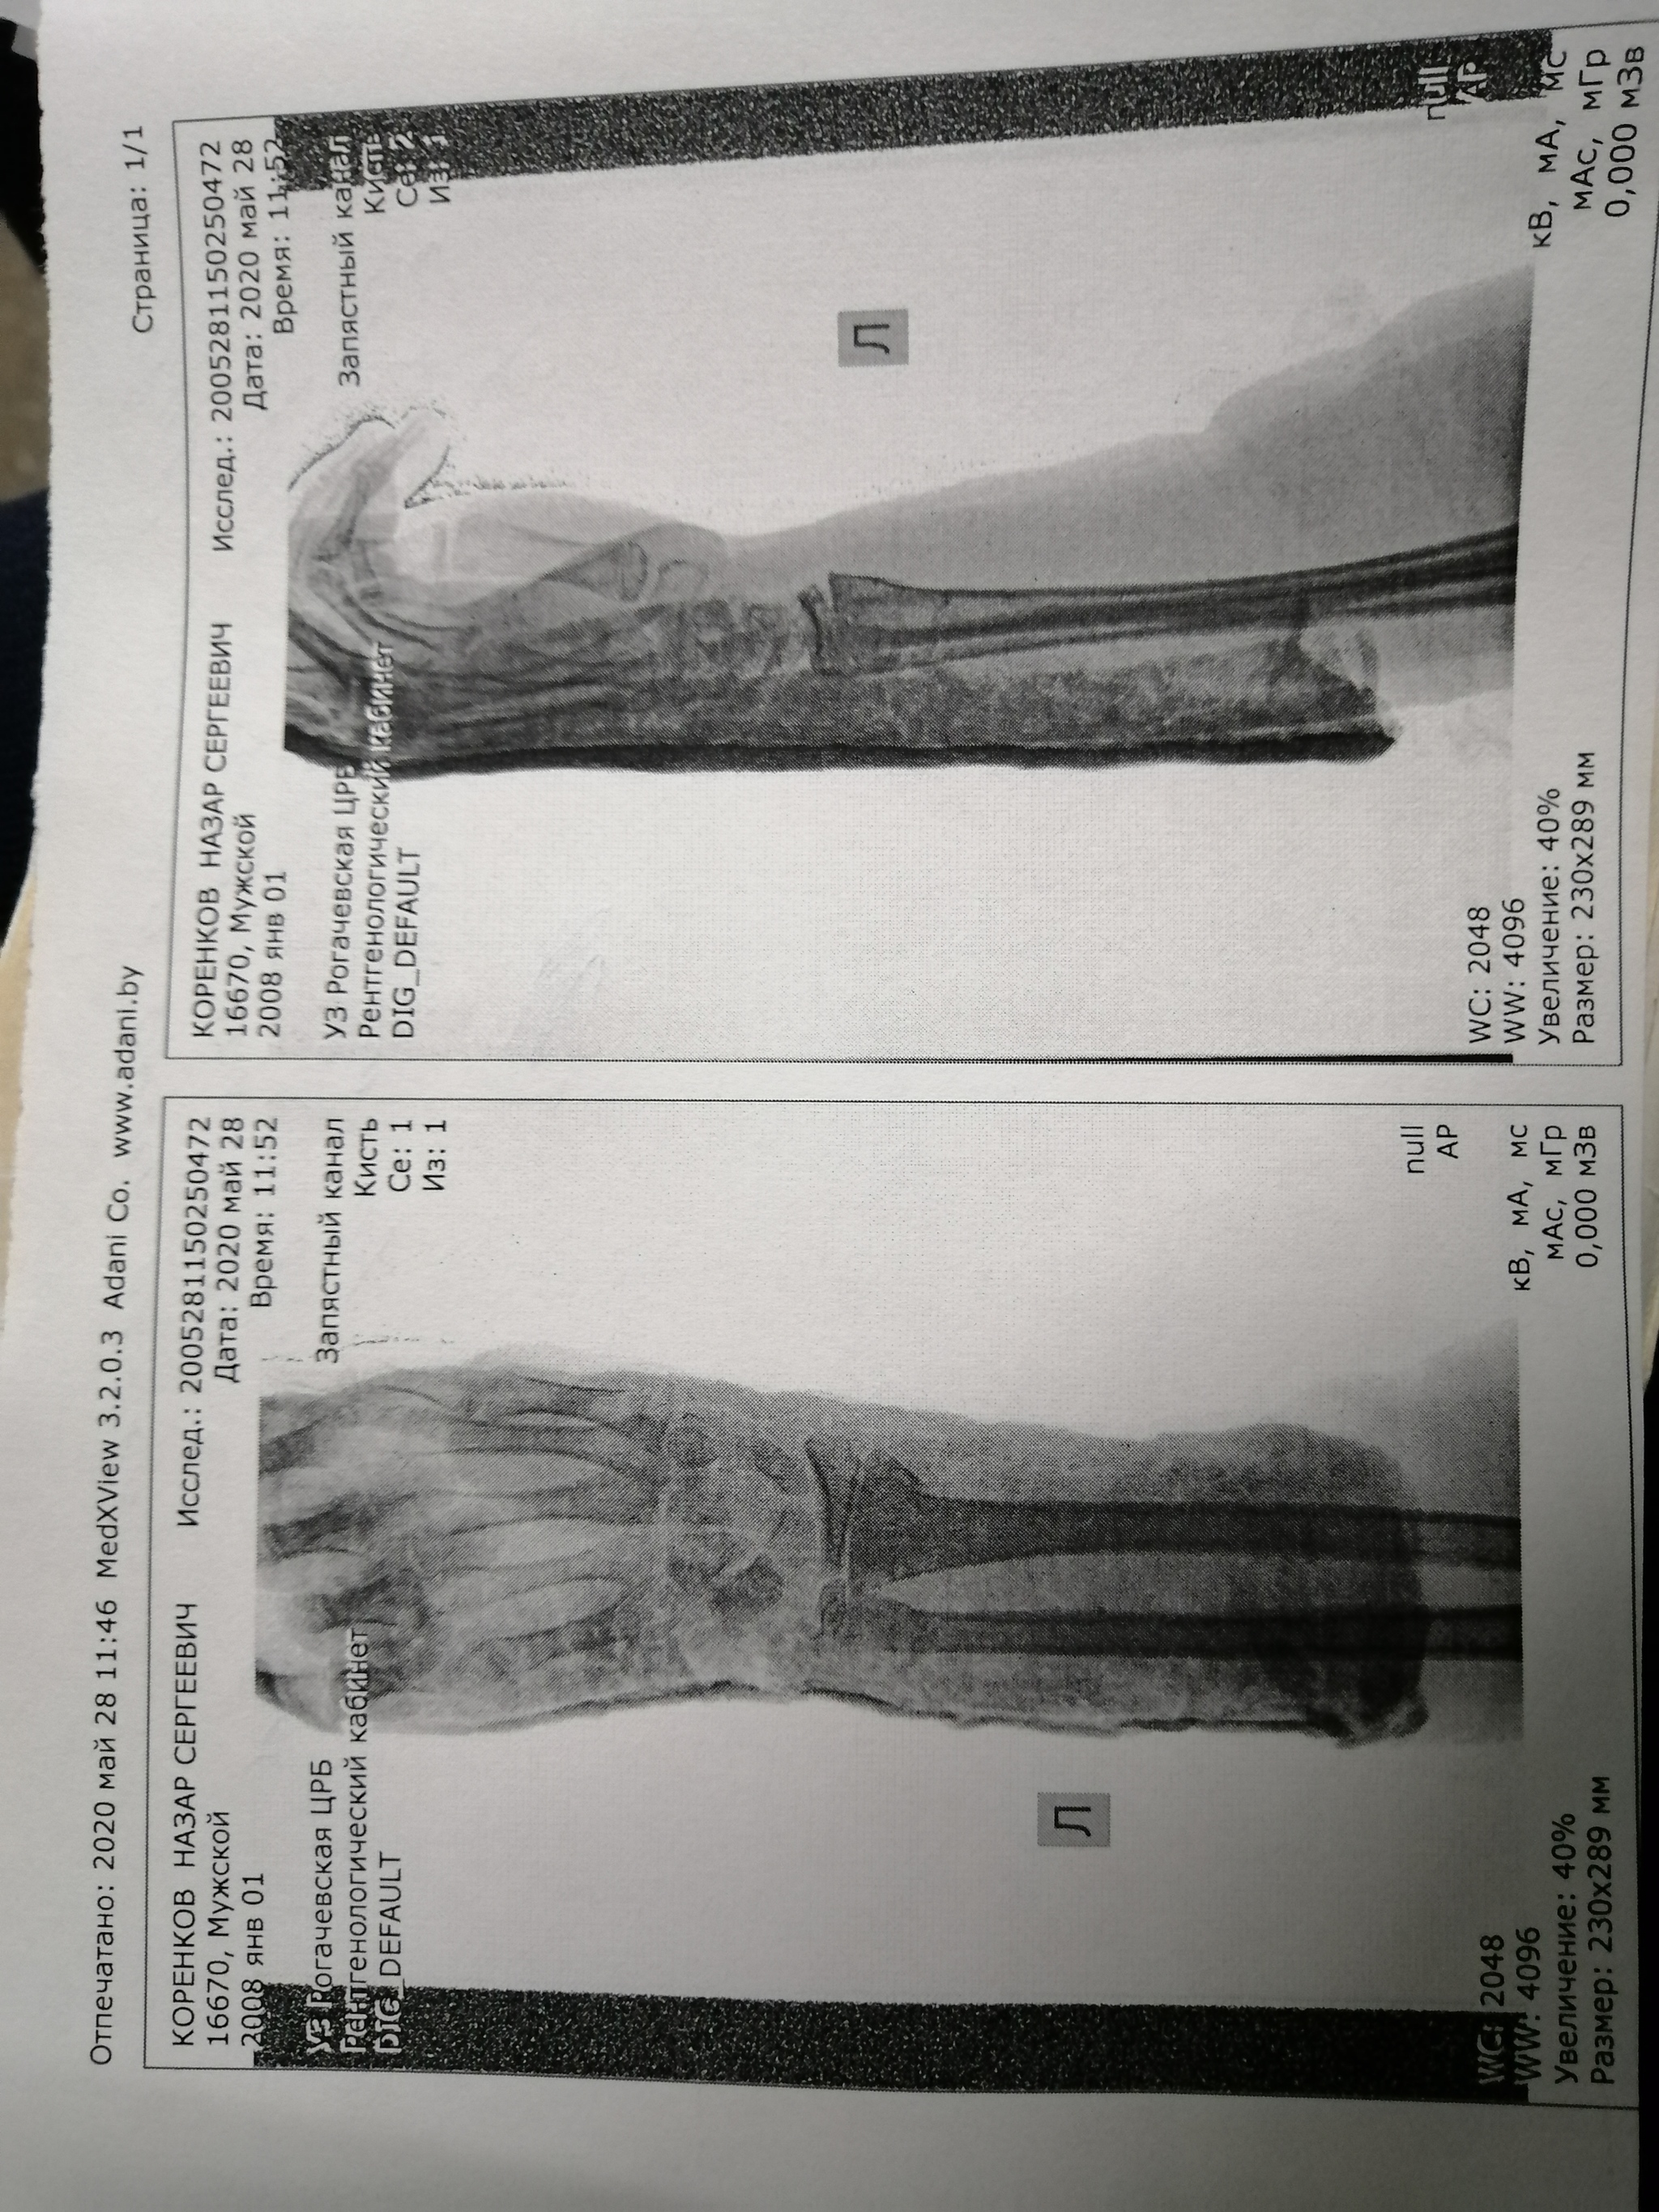

Снимок через две недели после перелома. До этого врач говорил, что кости срастаются правильно. Как так?

Перелом